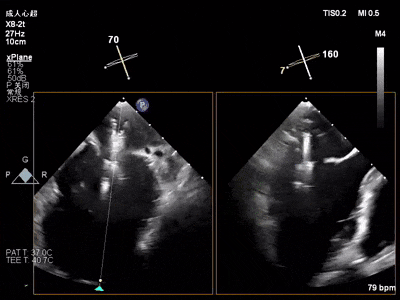

术中超声要点

术前术后对比图

术前

术后

术后,出院检查报告显示:夹子位置固定,二尖瓣轻度反流,左室稍大,LVEF值正常范围,左室壁运动分析未见明显异常(左室壁运动记分指数1分)